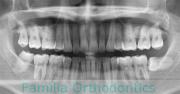

No.22V-029

- 叢生

- 上顎前突

- 19歳

- 男性

- 8448

- FEA 022

- 92万円

でこぼこを治したいということで来院されました。上下左右から親知らずも第一小臼歯も抜歯が必要で、歯科矯正アンカースクリューを併用して大臼歯を後ろに引っ張りながらの治療でした。3年弱、35回程度の通院が必要でした。

叢生が著しく、後戻りのリスクがあります。またアンカースクリューが必須のため、もしもスクリューが安定しないと、治療が難しく長くなってしまう恐れがありましたが、幸い脱落は見られませんでした。